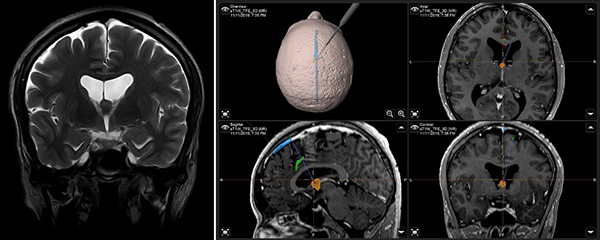

Paciente masculino de 40 años, sin antecedentes patológicos, atendido en nuestra institución por presentar cuadro de 2 años de evolución caracterizado por cefalea holocraneana de moderada intensidad, intermitente. Dos meses previo a la consulta inicial había presentado pérdida de consciencia más un episodio de crisis convulsiva tónico-clónico generalizada. Al examen físico el paciente no presentaba deterioro del sensorio ni déficit neurológico evidente. El resto del examen no mostraba hallazgos relevantes. La resonancia magnética (IRM) evidenció una lesión ovoidea que ocupaba el foramen de Monro, isointensa respecto al parénquima cerebral en las secuencias T1 y T2, de 12x9x9 mm, su margen rostral y dorsal en contacto con el pilar anterior y cuerpo del fornix, respectivamente; con tenue realce a la administración del contraste. En la secuencia de tensor de difusión los diferentes tractos se aprecian con trayecto normal y adecuada disposición de las fibras. Sistema ventricular sin dilatación ni compresiones. Se realizó la exéresis total de la lesión a través de un abordaje interhemisférico transcalloso anterior guiado por sistema de neuronavegación (Figura 1). El curso postoperatorio transcurrió con una hemiparesia braquio-crural derecha transitoria, que cede en días subsecuentes con recuperación total de la fuerza muscular. El paciente fue dado de alta sin déficit neurológico agregado. El examen patológico reportó un quiste coloide. La IRM postoperatoria confirmó la extirpación total de la lesión con cambios postquirúrgicos asociados a craneotomía fronto-parietal derecha (Figura 2). El paciente se encuentra asintomático en seguimiento por la consulta externa.

Figura 1. (A) IRM T2W coronal: ubicación anatómica de la lesión en foramen interventricular; (B) IRM integrada al sistema de neuronavegación, planeación de abordaje quirúrgico.

Paciente en decúbito dorsal, fijación con cabezal de Mayfield en posición neutra con ligera flexión y elevación de la cabeza respecto al tórax, rotación aproximada de 15° para que por gravedad separe al hemisferio derecho. Planificación con neuronavegador (sistema BrainLab Curve) utilizando IRM en secuencias T1 y T2 para definir estructuras vasculares importantes, en este caso el seno longitudinal superior (SSS) y arterias cerebrales anteriores con sus ramas pericallosas y calloso marginal, así como vascularización del tumor, que están presentes en el abordaje quirúrgico. Diéresis en herradura, incidiendo por planos logrando exposición ósea hasta identificar la sutura coronal y sagital. Craneotomía practicada en forma de herradura, situándose ⅔ delante y ⅓ detrás de la sutura coronal sobrepasando al menos 1 cm la línea media para exponer y desplazar al SSS y lograr una mejor exposición de la fisura interhemisférica (Figura 3).